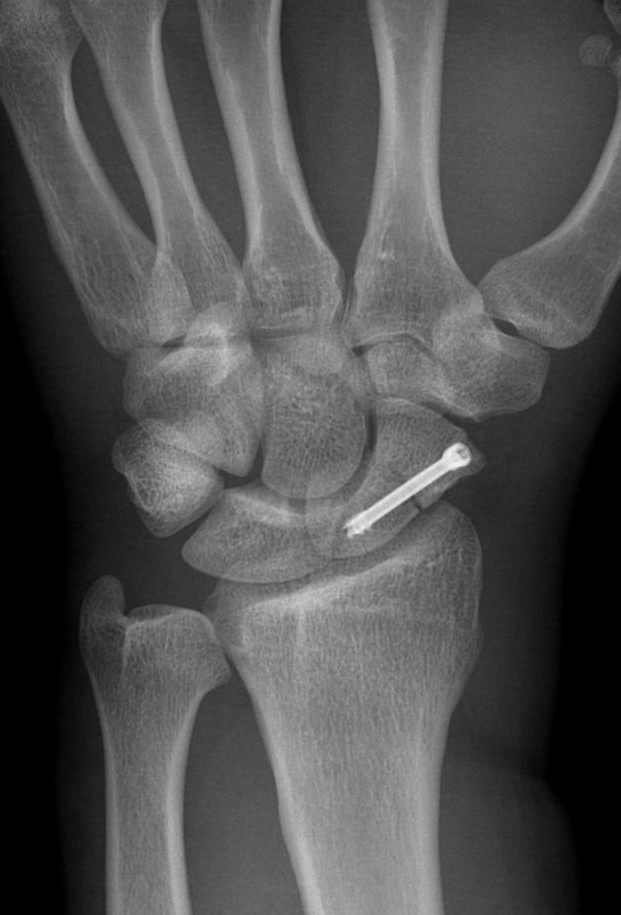

Feldman G, Orbach H, Rozen N, Rubin G. Usefulness of prophylactic antibiotics in preventing infection after internal fixation of closed hand fractures. Hand Surg Rehabil 2021;40(2):167-70.

Ridley TJ, Freking W, Erickson LO, Ward CM. Incidence of treatment for infection of buried versus exposed Kirschner wires in phalangeal, metacarpal, and distal radial fractures. J Hand Surg Am 2017;42(7):525-31.